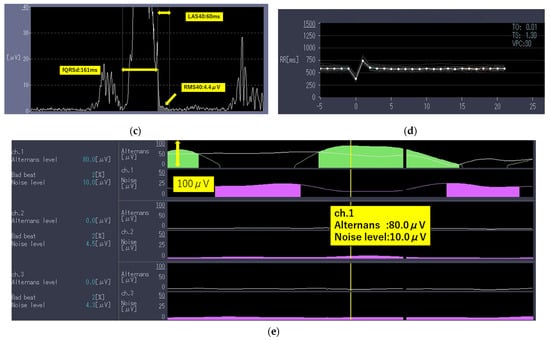

A 76-year-old man complaining of dyspnea was hospitalized after being diagnosed as having COVID-19 using a real-time polymerase chain reaction test. He had a history of hypertension, diabetes mellitus, and cerebral infarction but no history of significant cardiovascular diseases. His vital signs upon admission are shown in Table 1. QT prolongation and ST-T changes are not shown (Table 1). The laboratory data gathered are summarized in Table 2. The findings indicate that the inflammatory markers for this patient were moderately to highly elevated. The chest radiographs (Figure 2a) and computed tomography images (Figure 2b) reveal extensive ground-glass opacities. The echocardiographic findings are shown in Table 3. A 24 h Holter electrocardiography performed upon admission showed that all AECG-Ms were positive (Table 4). The patient was treated with heparin at a dose of 14,000 U/day for 12 days, remdesivir at a dose of 200 mg/day for 10 days, and dexamethasone at a dose of 6.6 mg/day for 10 days. However, his dyspnea worsened, the chest radiographs showed spreading ground-glass opacities, and he died from respiratory failure on day 12 after admission.

Figure 2.

Imaging findings of Case 2 captured on day of admission. (a) Chest radiograph and (b) chest computed tomography image showing bilateral diffuse ground-glass opacities.